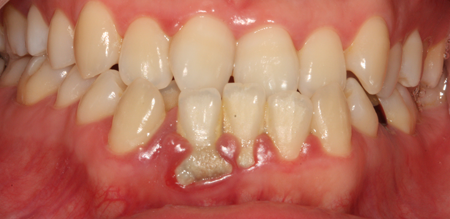

치주치료 전후사진

B

A